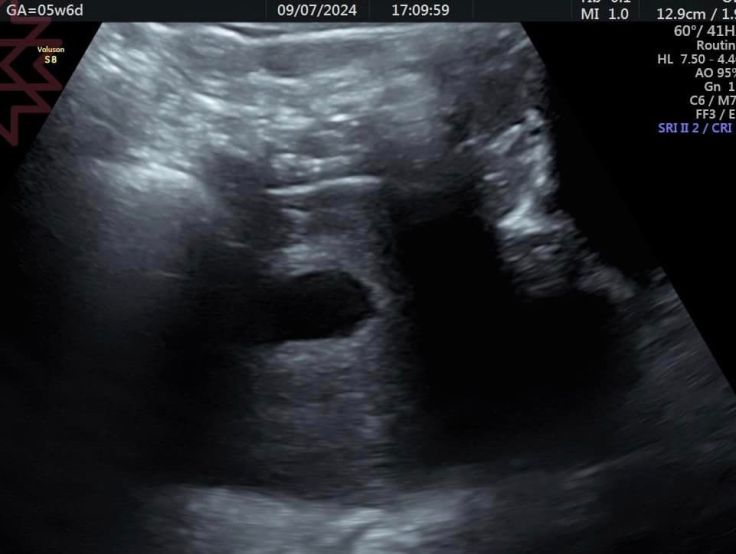

這是同一個媽咪同一天的超音波

超音波的第一張是從腹部超音波看到的

基本上只能看到一個小胚囊